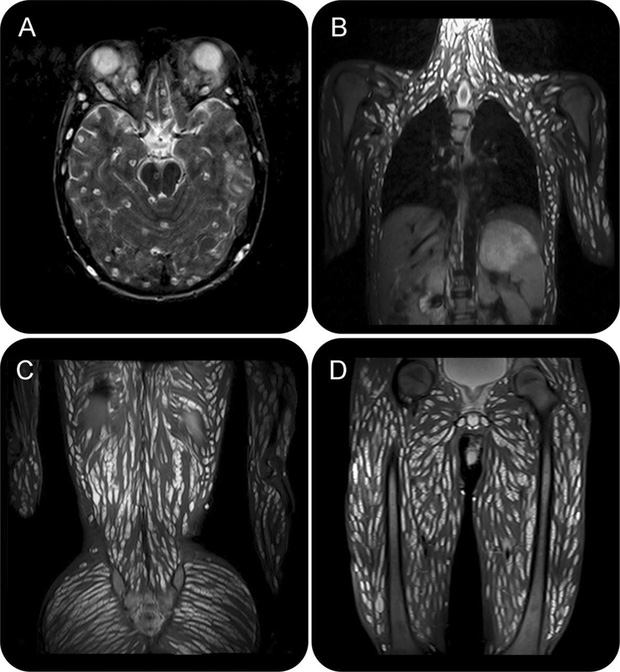

Sau khi được kiểm tra bằng phương pháp chụp cộng hưởng từ cho thấy các mô não, đầu, ngực, bụng và chân tay của chàng thanh niên này đều bị ký sinh bởi lượng lớn sán dây. Nếu nhìn vào các ảnh chụp cộng hưởng cơ thể của bệnh nhân, có thể thấy toàn bộ cơ thể bị bao phủ bởi các dải màu trắng, nhìn rất đáng sợ.